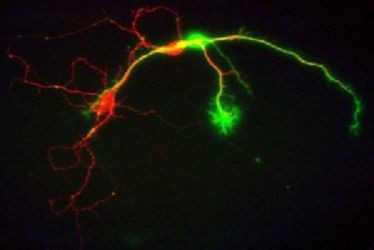

Neuroscience Colloquium Münster

Neuroscience Colloquium Münster

Neuroscience Colloquium Münster

Neuroscience Colloquium Münster

Neuroscience-Colloquium Münster

Neuroscience-Colloquium Münster

Neuroscience Colloquium Münster

Neuroscience Colloquium Münster

Neuroscience Colloquium Münster

Neuroscience Colloquium Münster

Neurologisches Seminar: Erkenntnisse aus der Neurogeneseforschung und Implikationen für die Klinik

Neurologisches Seminar: Erkenntnisse aus der Neurogeneseforschung und Implikationen für die Klinik

Neuroscience Colloquium Münster

Neuroscience Colloquium Münster

Neuroscience Colloquium Münster

Neuroscience Colloquium Münster

Neuroscience Colloquium

Neuroscience Colloquium